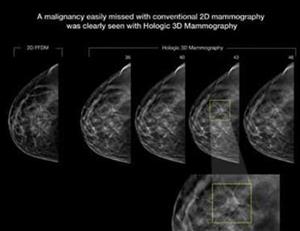

With a continued and dedicated interest in supporting and caring for the women in our community, Sansum Clinic has – with the help of gifts from grateful patient – invested in new 3D Mammography technology, or Breast Tomosynthesis. Our standard 2D digital mammographic imaging has been, and is, an amazing tool for the early detection of cancers. Upgrading to this new 3D technology, the Selenia Dimensions from Hologic®, can help us detect cancers much earlier and those cancers can be caught when they are much smaller, making them easier to treat. A recent article, “Breast Cancer Screening Using Tomosynthesis in Combination with Digital Mammography” from the Journal of the American Medical Association (JAMA, June 25, 2014) highlights the distinct benefit of the technology after a total of 454,850 examinations (281,187 conventional mammograms compared to 173,663 3D mammograms) were conducted. A few of the significant findings are:

- A 41% increase in the detection of invasive breast cancers

- A 29% increase in the detection of all breast cancers

- A 15% decrease in women recalled for additional imaging

An increase in the number of cancers detected is significant and the benefit may seem obvious to those reading this article. Maybe not so obvious in significance is the decrease in the number of women recalled for additional imaging. This means that we can effectively reduce the radiation exposure from additional imaging, and perhaps more importantly, reduce the worry, anxiety and stress among our patients associated with those callbacks.